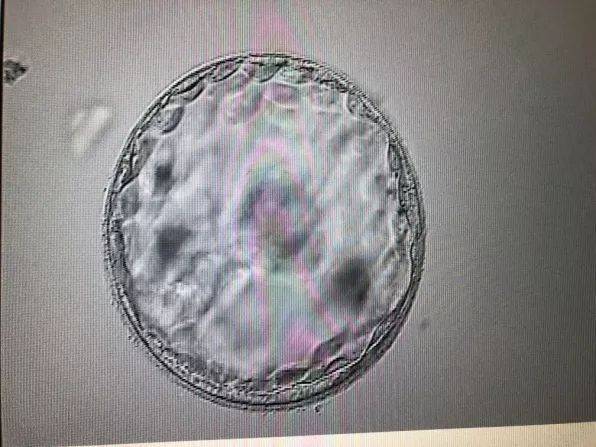

妊娠期糖尿病